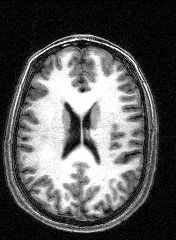

The images to the right are virtual 'slices', taken horizontally, starting from the top and working down. Cerebrospinal fluid is dark, the white matter appears light.

Medical images such as these are easy to come by on the internet, but having images of your own brain brings a humbling perspective.